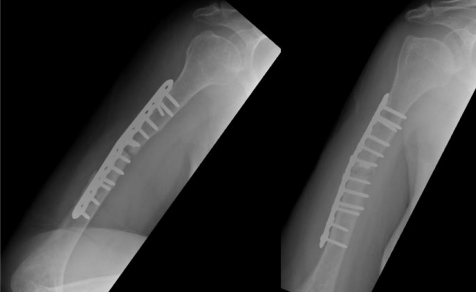

At that time, the primary surgeon decided to transfer the case to the Trauma unit, where the patient was reviewed thoroughly and all necessary investigations was made, after detailed discussion of the case and the options, we decided to go for another revision but with some tactical modifications. The patient was taken for yet another surgery, for the fifth time (fourth revision) on 30 November 2020. The same incision site was used, and the previous plate was removed and sclerotic bone debrided. An intramedullary cancellous bone graft was obtained from the patient’s left femur with the aid of a reamer-irrigator-aspirator. A titanium mesh cage was used to bridge the bone defect, and the graft from the left femur intramedullary canal was packed inside the titanium mesh cage. Primary fixation was obtained with a long proximal humerus locking plate laterally and augmented with a 3.5 cm locking compression plate anteriorly sat 90 degrees orientation.

Finally, 5.6 mL of rhBMP-2, on an absorbable collagen sponge carrier (ACS), was applied to the nonunion site. Postoperative radiographs are shown in Figure 8. Postoperatively, the patient suffered radial nerve neuropraxia, managed with splinting, and fully recovered 5 months postoperatively. Serial follow-ups for 21 months postoperatively showed complete healing clinically and radiographically, restoration of functional range of motion with the help of physiotherapy, and a painless functional limb. Radiographs are shown in Figure 9.

Figure 08

Figure 09